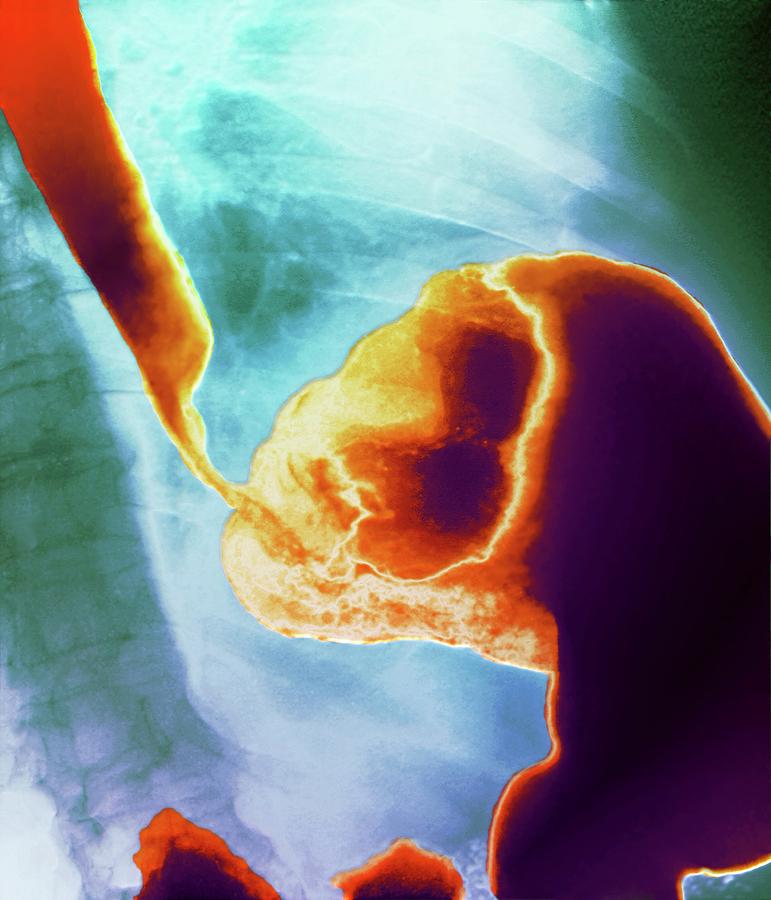

Stomach cancer, Barium X-ray – Stock Image – C004/1368 – Science Photo …

Coloured X-ray of stomach cancer (carcinoma) – Stock Image – M134/0307 …

Contrast radiography of our patient on their initial visit. Scirrhous …